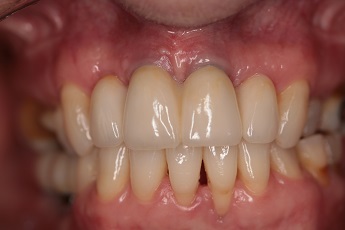

![]() |

Foto 29, 30: Stav před ošetřením a po vytvoření a umístění definitivního můstku na implantátech v chrupu.